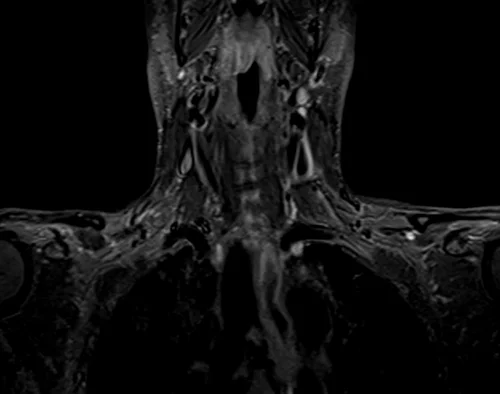

BRACHIAL PLEXUS